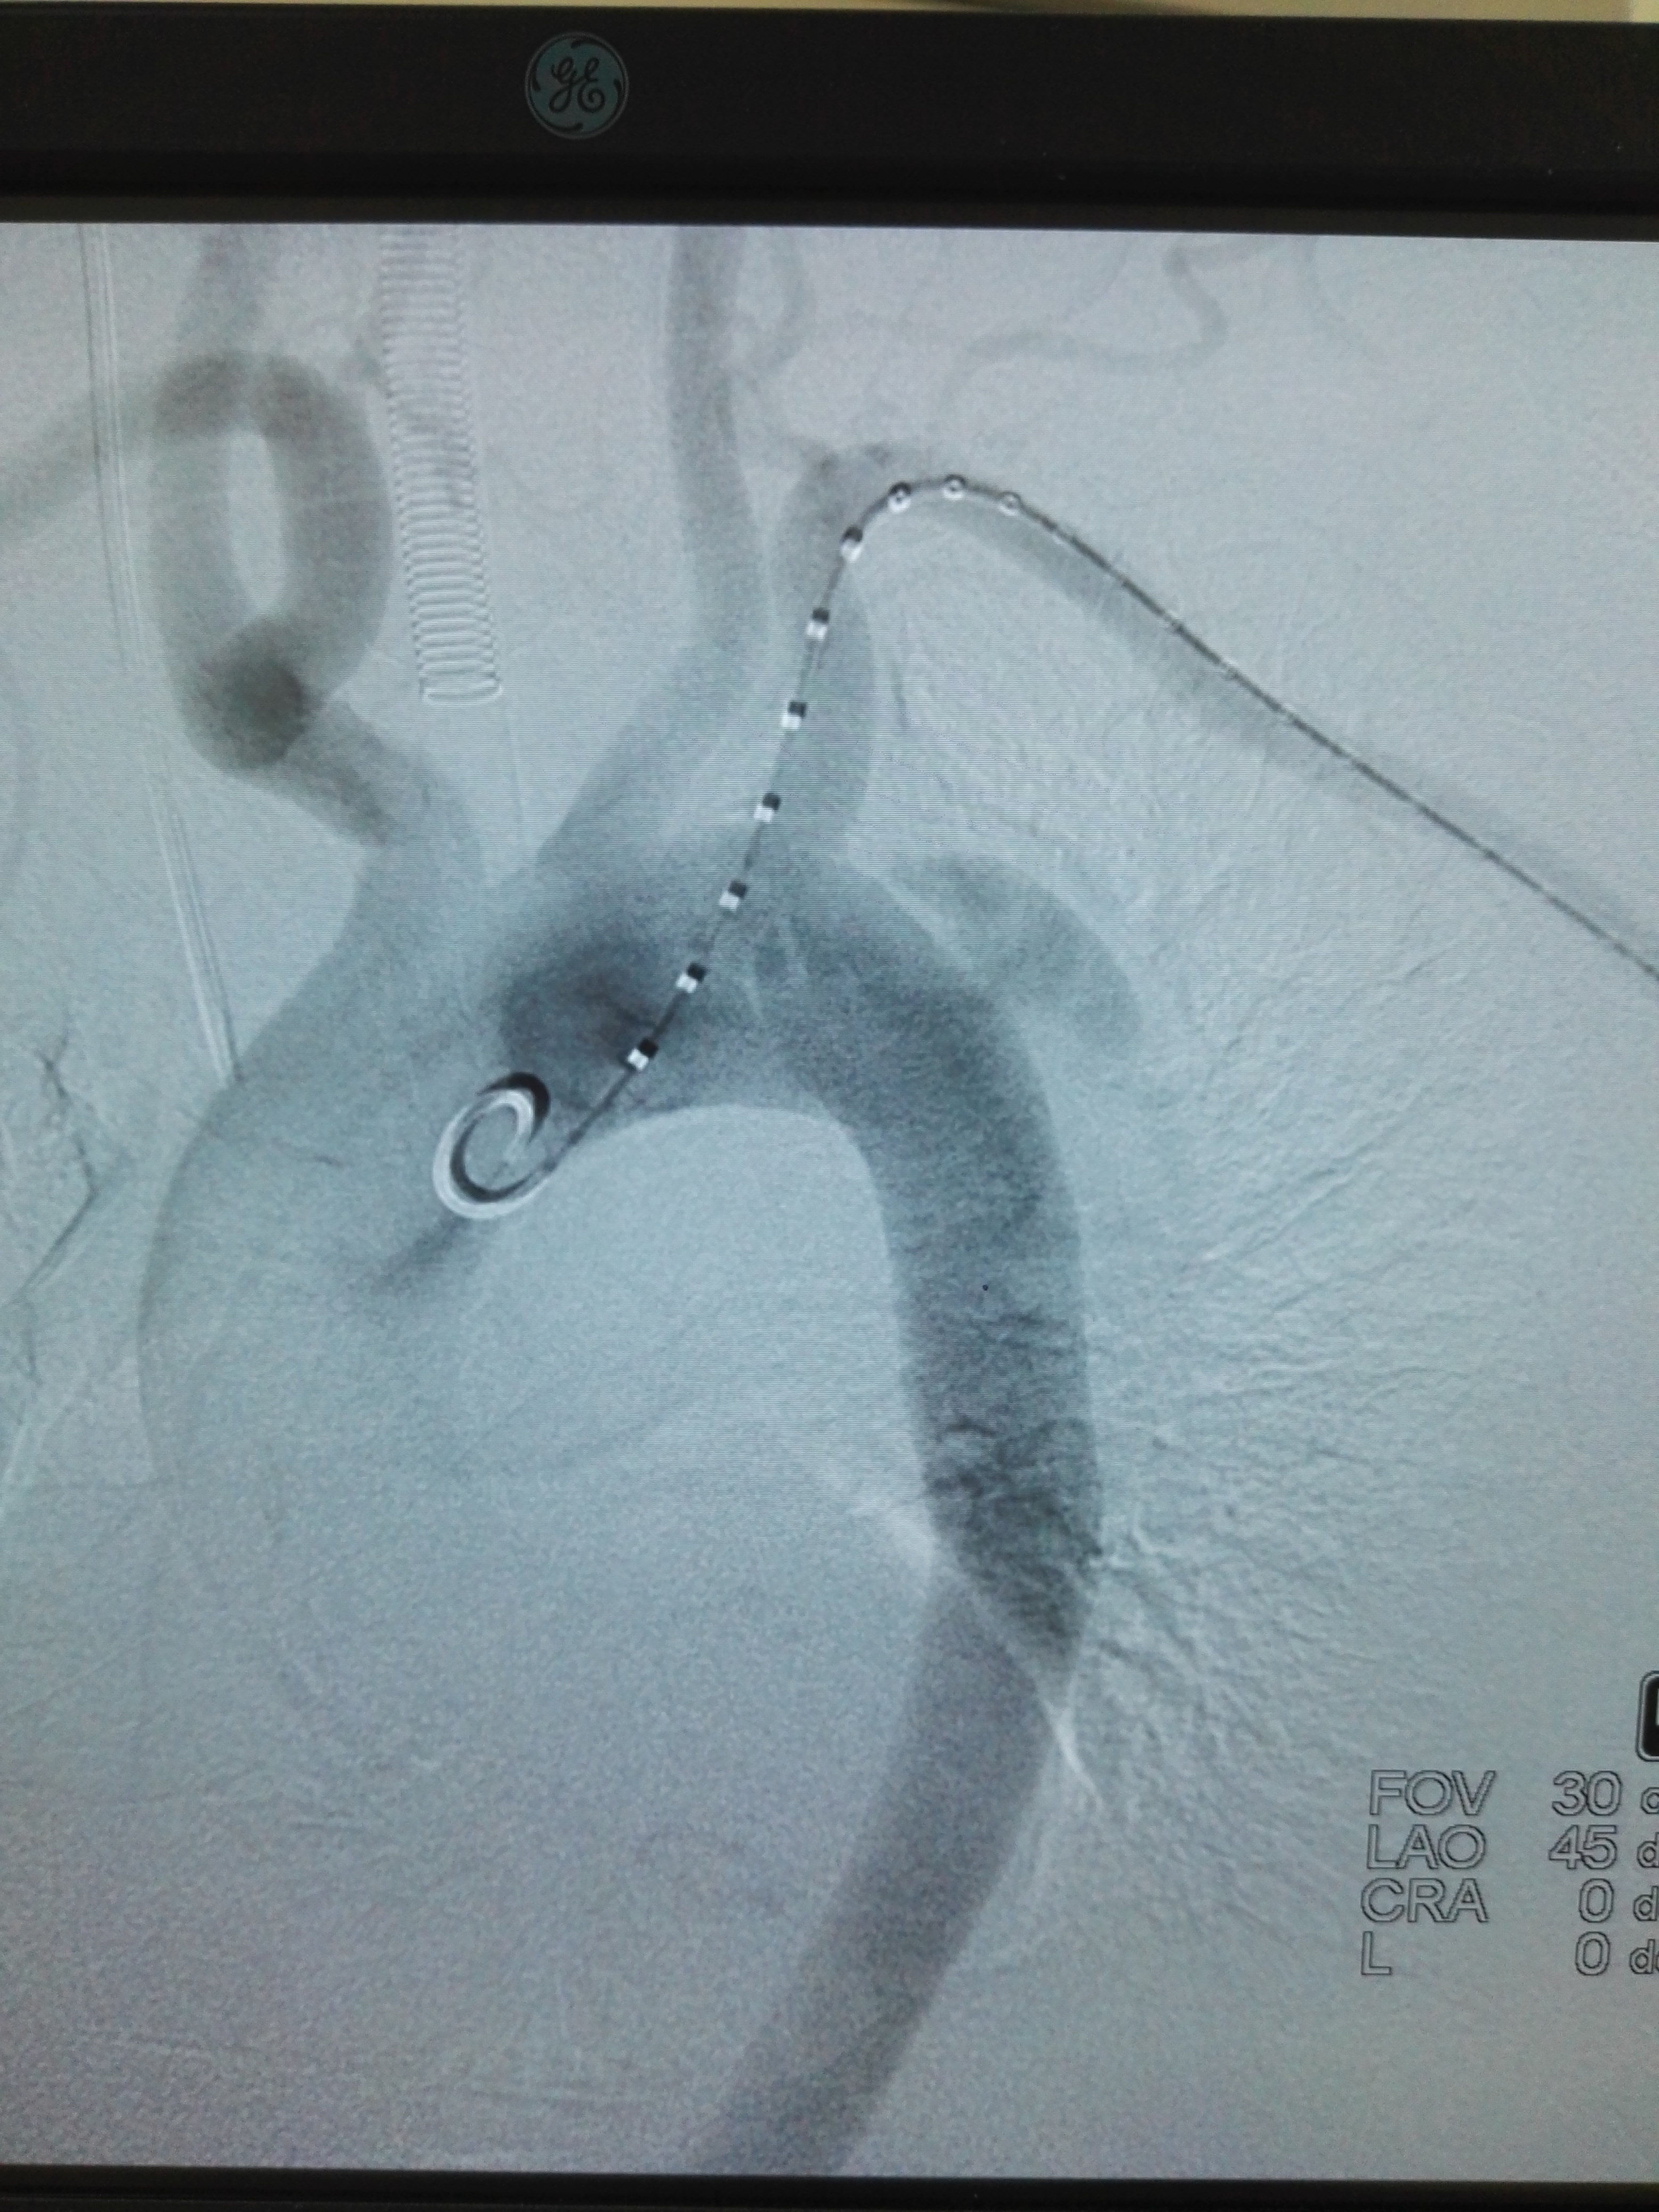

stanford b型主动脉夹层腔内治疗的观察研究

图片尺寸259x267

急性创伤性stanford b型主动脉夹层的早期诊断及腔内修复治疗

图片尺寸425x250